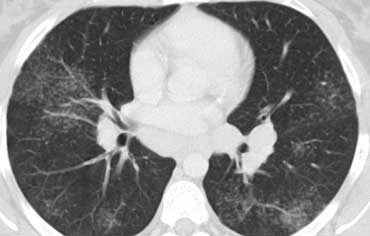

Hình bên trái là bệnh nhân suy giảm miễn dịch mắc PCP.

Hình ảnh CT cho thấy mờ dạng kính mờ lan tỏa.

Hình ảnh này không đặc hiệu cho PCP, nhưng trong bối cảnh lâm sàng này, PCP là chẩn đoán có khả năng cao nhất.

Hình bên trái là một bệnh nhân khác mắc PCP.

Cuộn qua các hình ảnh để xem.